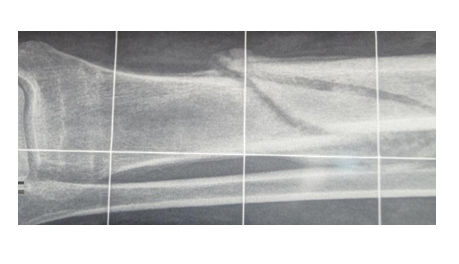

Compared with the indicators of patients in group 1, the duration of the fixation of bone fragments in patients treated on an outpatient basis increased from 59±2 to 94±7 days (p≤0.001). The cross-sectional area of the tibial periosteal callus in patients of the 1st group was respectively 45±15 (in 20% of cases it was not determined), in patients treated on an outpatient basis, the rate reached 213±25 mm2 (p≤0.001) (Figure 1 & 2).

Figure 1 Radiograph of the tibial bone of the patient K-th -31 year, after the end of inpatient treatment. The term of fixation is 50 days, the area of periosteal corn is -25 mm2.

Figure 2 Radiograph of b-go G-va 29 years, after outpatient treatment, the term of fixation 120 days, the area of periosteal corn 1080 mm2.